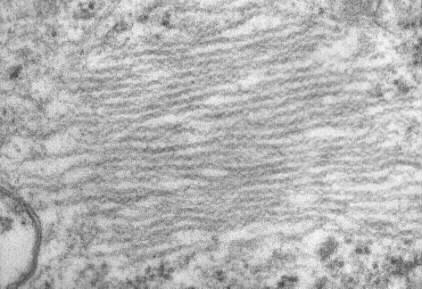

Enlarged view

Enlarged longitudinal section of the paired twisted filaments

(PTF), peculiar double helical structures, 12 to 25 nm in maximal helix

width with a half periodicity of 30 to 35 nm (periodicity of the constrictions),

in a human pinealocyte (original x74,000). These PTF were first

reported in human pinealomas by Hassoun et al (Acta Neuropathol, 65;

163-165, 1984) and similar structures have been described only exceptionally

in spinal ganglia (van den Bosch et al, in Virchows Arch [Cell Pathol],

47; 217-222, 1984) and cerebral neurons (Knox et al, in Acta Neuropathol,

52; 7-15, 1980) of aged rats. The biological and pathological implications

of the PTF remain unclear.